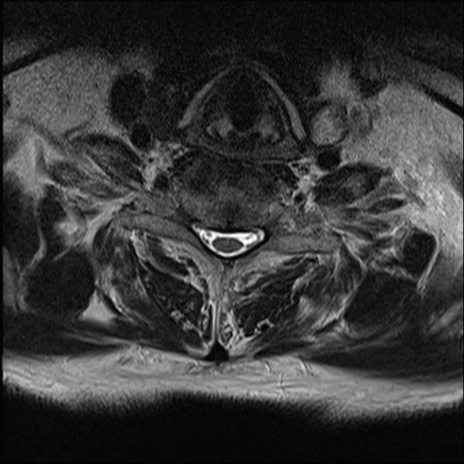

【整形】TIPS症例7 頚椎MRI T2WI(横断像)

頚椎MRI

矢状断像と横断像